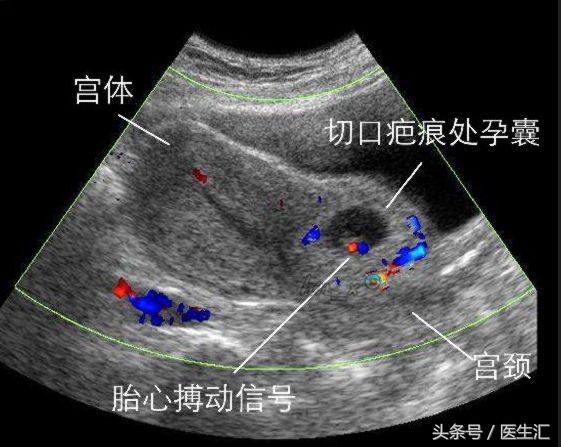

2.超声检查是最有效和可靠的工具,早期妊娠时子宫颈管及宫腔均正常,子宫峡部前壁有包块,向前隆起,贴向膀胱,外缘距浆膜层薄,一般均小于5mm,最薄1~2mm。

B超图象中孕囊呈低回声,偶见胚芽及心管搏动,若浆膜层破裂,腹腔内有积液。彩色多普勒可见孕囊周围有丰富彩声血流信号.